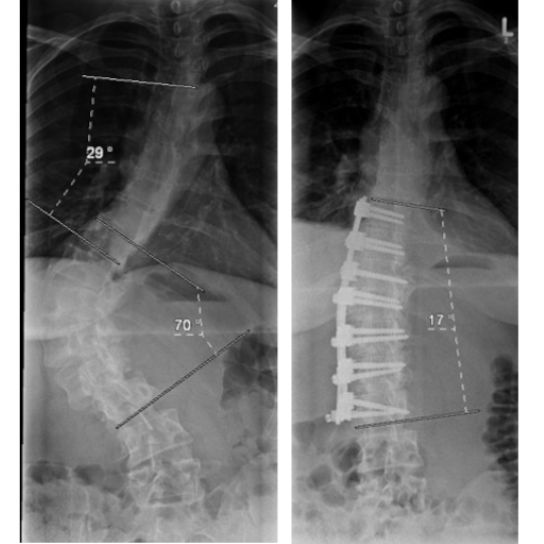

Ventrale Skoliose-Operation

Bei der Operation von ventral, also von vorne, wird entweder durch den Brustkorb oder den Bauch mit seitlichen Zugängen der vordere Anteil der Wirbelsäule erreicht. Diese Methode war bis vor einigen Jahren sehr populär, weil besonders kurzstreckig operiert werden konnte. Sie eignet sich jedoch nur für einbogige Krümmungen der Brust- oder Lendenwirbelsäule und hat den Nachteil, dass der Brustkorb geöffnet werden muss, wovon man sich einige Zeit erholen muss.

16 jähriger Junge mit primär thorakaler Krümmung